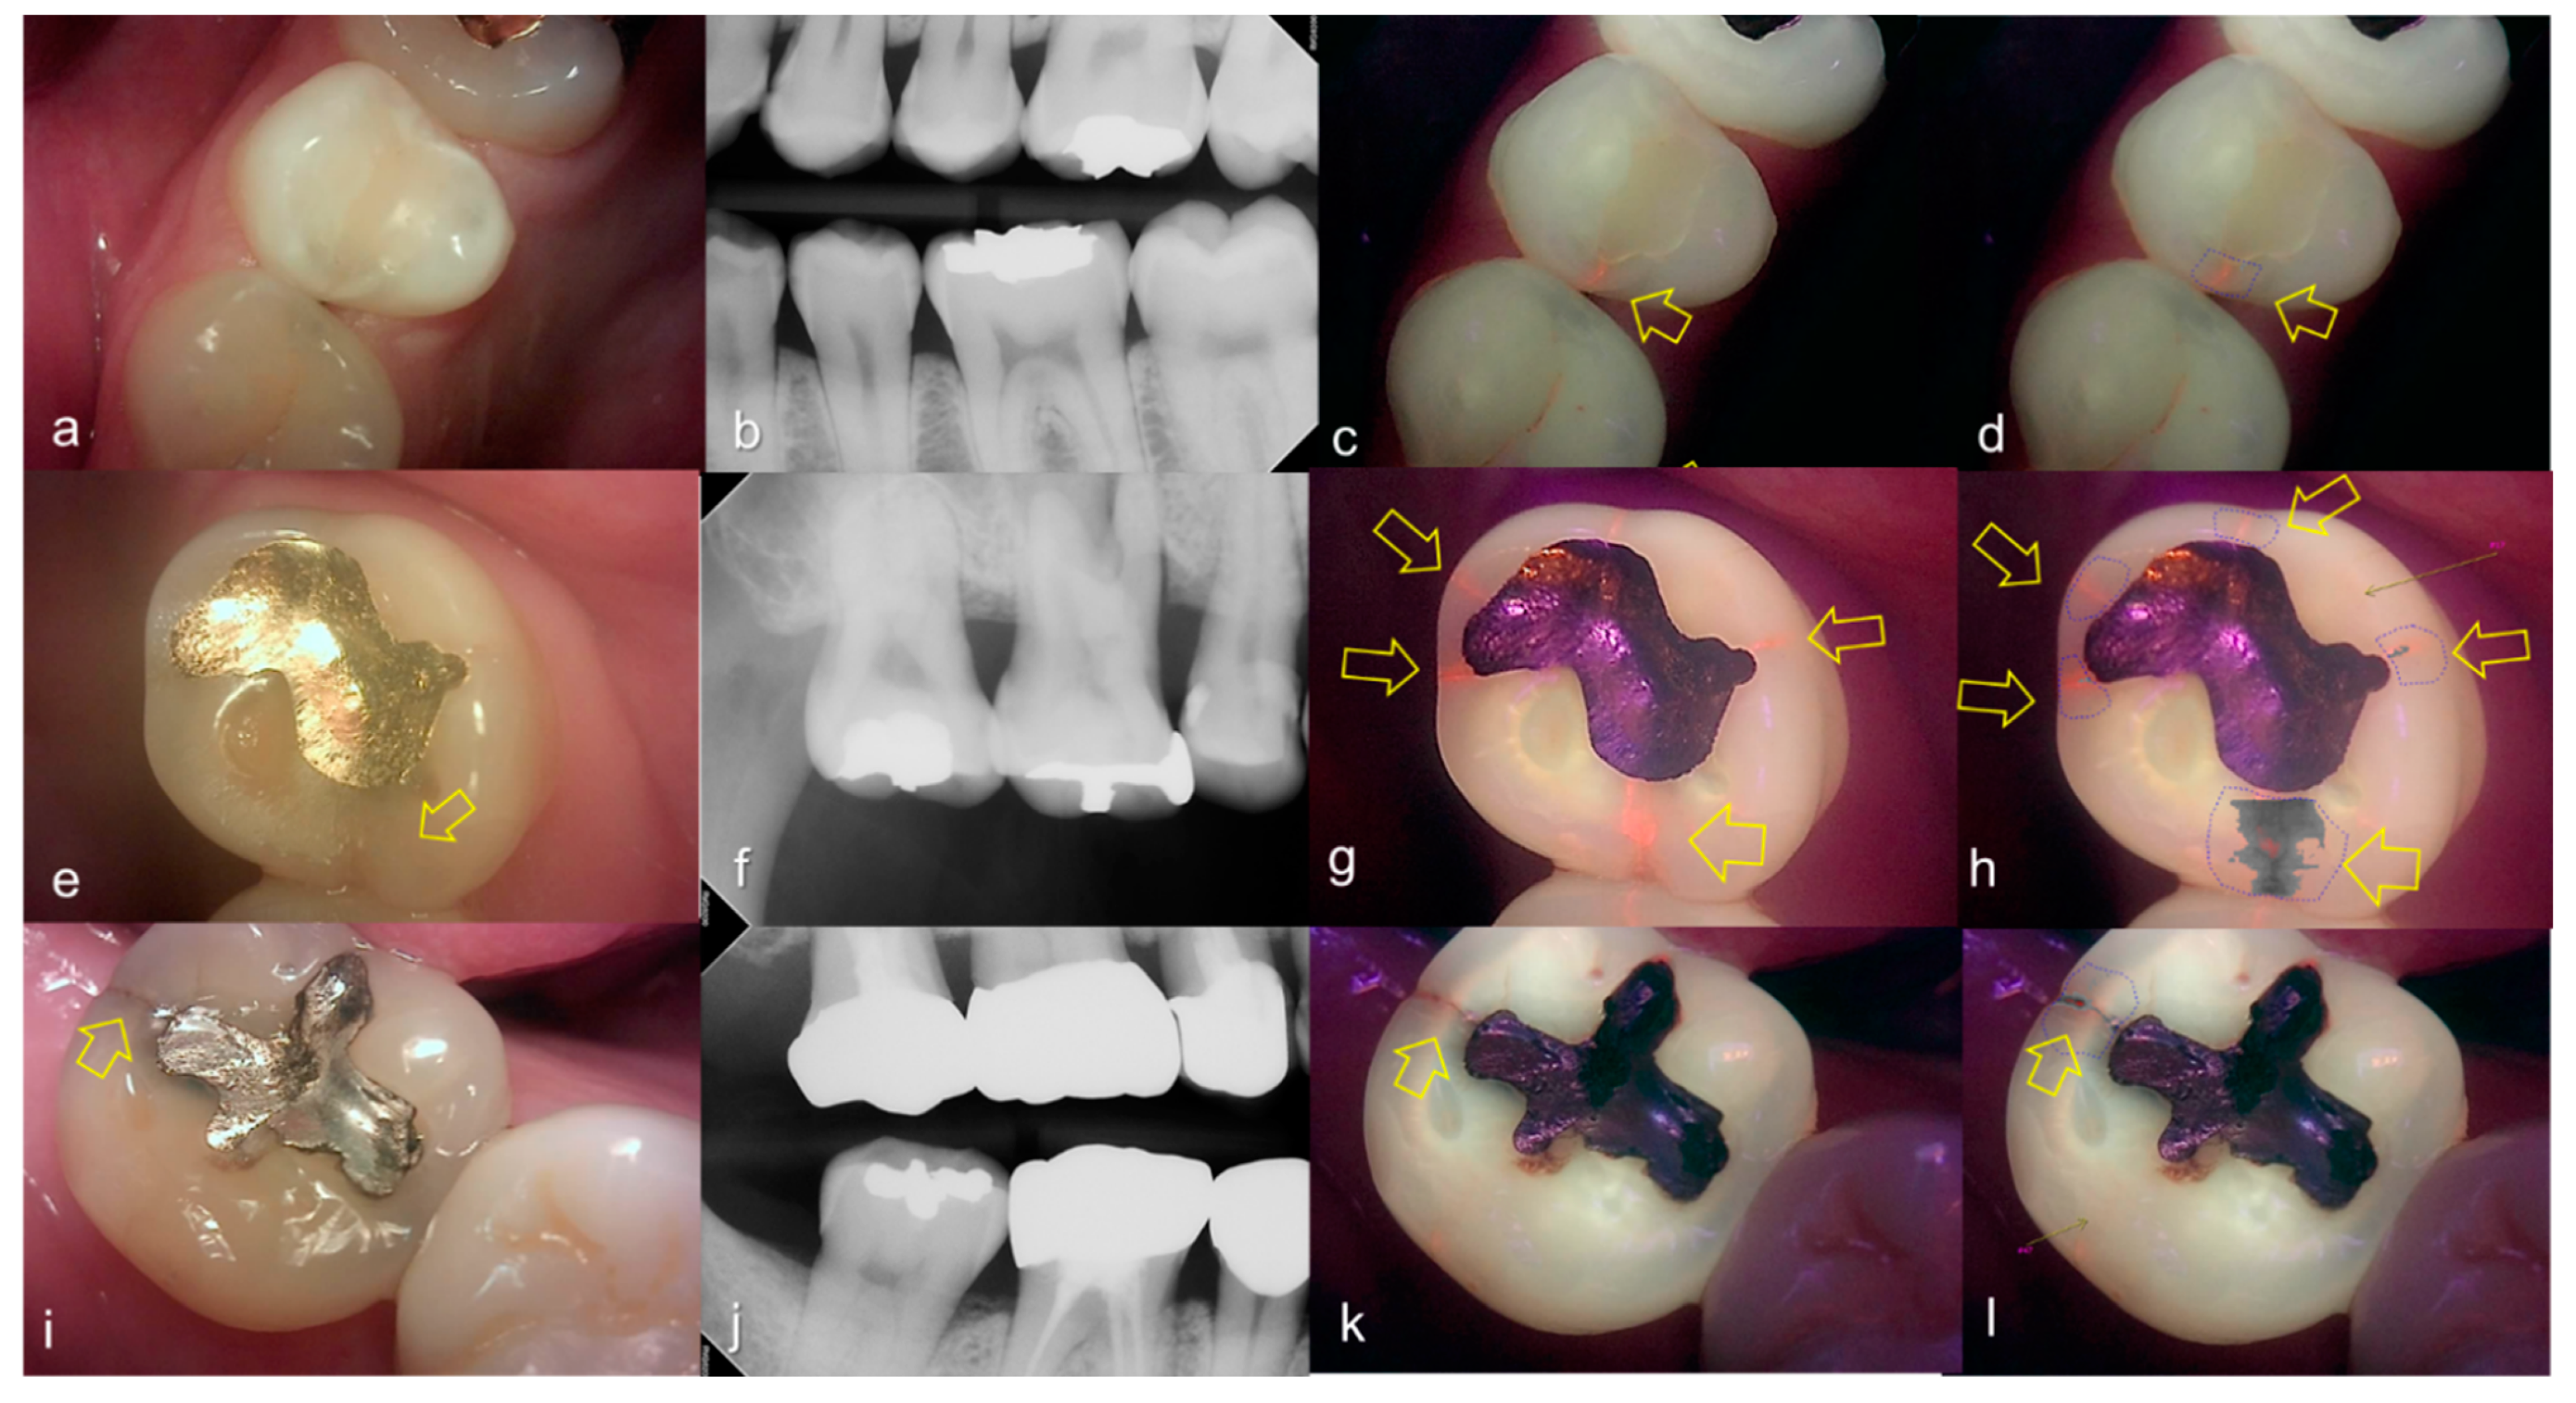

Evaluating proximal dental caries according to the QLF criteria and X-ray criteria, moderate positive correlation was observed (r = 0.63, p < 0.0001). Among the QLF parameters classified based on X-ray criteria, the |ΔFmax| value increased significantly as the score value increased from 1 to 4 (from 3.12 to 19.56). In particular, |ΔFmax| was about 5.7-fold higher for proximal dental caries score = 3 (17.64) than proximal dental caries score = 0 (3.12), and the maximum loss of fluorescence was 6.3-fold higher for the proximal dental caries score = 4 (19.56) (Table 2). The cut-off value of |ΔFmax| for detecting proximal dental caries (X-ray criteria scores 0 and 1 vs 2–4) was 5.95. The sensitivity, specificity and AUROC of parameter were 0.74, 0.73 and 0.81, respectively. However, the sensitivity, specificity and AUROC of the parameter ΔRmax were 0.83, 0.00 and 0.59 (Table 3). Representative images of QLF and bitewing radiograph of proximal dental caries are shown in Figure 6, Figure 7 and Figure 8.

Figure 6.

Proximal dental caries: (a–d) QLF caries score 0 (no fluorescence loss and no red fluorescence increase in occlusal surface (distal side)) and radiographic caries score 1 (radiolucency visible in the enamel) on #14 and QLF caries score 0 (no fluorescence loss and no red fluorescence increase in occlusal surface (mesial side)) and radiographic caries score 2 (radiolucency in the dentine but restricted to the outer 1/3 of the dentine) on #15; (e–h) QLF caries score 1 (fluorescence loss and red fluorescence present in occlusal surface (distal side)) and radiographic caries score 2 (radiolucency in the dentine but restricted to the outer 1/3 of the dentine) on #14 and QLF caries score 0 (no fluorescence loss and no red fluorescence increase in occlusal surface (distal side)) and radiographic caries score 2 (radiolucency in the dentine but restricted to the outer 1/3 of the dentine) on #15; (a,e): white-light image of QLF; (b,f): fluorescence image of QLF; (c,g): bitewing radiograph; (d,h): analyzed QLF image using QA2 software.

Figure 7.

Proximal dental caries: (a–d) QLF caries score 0 (no fluorescence loss and no red fluorescence increase in occlusal surface (distal side)) and radiographic caries score 3 (radiolucency extending to the middle 1/3 of the dentine) on #16; (e–h) QLF caries score 2 (fluorescence loss and red fluorescence glow extending around occlusal surface (distal side)) and radiographic caries score 3 (radiolucency extending to the middle 1/3 of the dentine) on #14; (i–l) QLF caries score 2 (fluorescence loss and red fluorescence glow extending around occlusal surface (distal side)) and radiographic caries score 3 (radiolucency extending to the middle 1/3 of the dentine) on #15; (a,e,i): white-light image of QLF; (b,f,j): fluorescence image of QLF; (c,g,k): bitewing radiograph; (d,h,l): analyzed QLF image using QA2 software.

Figure 8.

Proximal dental caries: (a–d) QLF caries score 0 (no fluorescence loss and no red fluorescence increase in occlusal surface (distal side)) and radiographic caries score 4 (radiolucency in the pulpal 1/3 of the dentine) on #26; (e–h) QLF caries score 2 (fluorescence loss and red fluorescence glow extending around occlusal surface (distal side)) and radiographic caries score 4 (radiolucency in the pulpal 1/3 of the dentine) on #25 (a,e): white-light image of QLF; (b,f): fluorescence image of QLF; (c,g): bitewing radiograph; (d,h): analyzed QLF image using QA2 software.